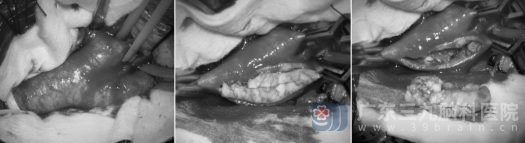

手术在显微镜下精准开展:仅通过颈部7cm的小切口,医生逐层分离组织,暴露颈动脉后,短暂阻断血流,切开血管壁,完整剥脱长约3cm的硬化斑块,再用肝素盐水仔细冲洗管腔,确保血管内膜光滑,最后精细缝合血管,全程几乎无额外损伤。

术中照片